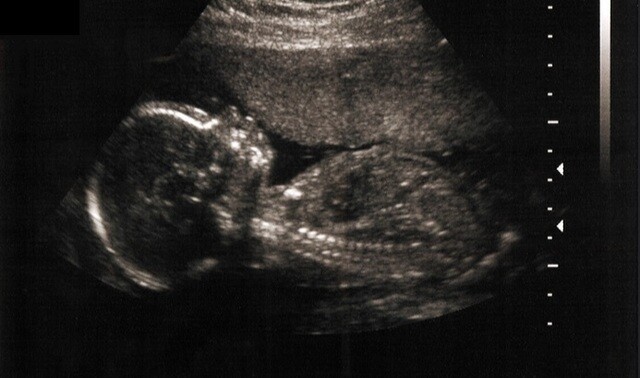

"I had one dead twin. The other had severe Spina Bifida, and would only have lived with life support, in great pain, for a few days.

"The abortion was terrible. It was done very gently, by Caesarean section, leaving the babies in their amniotic sacs. The living baby passed very quickly.